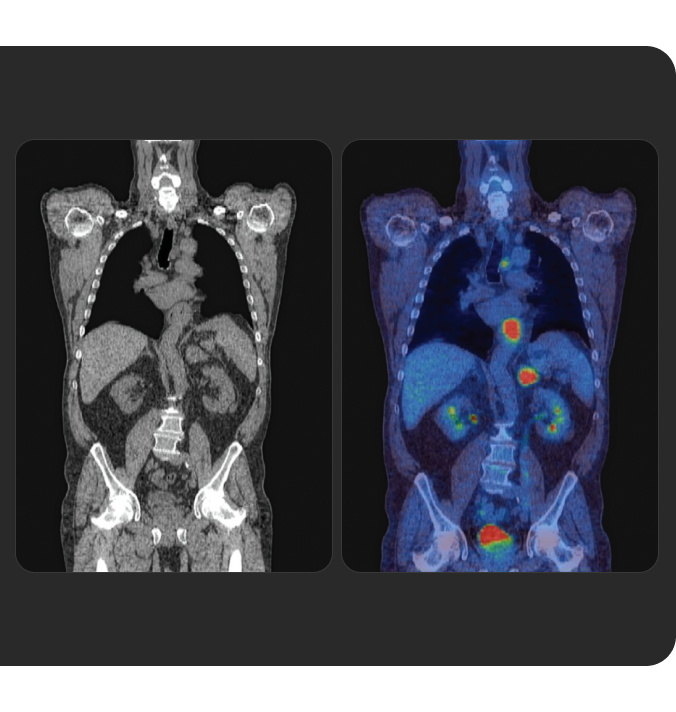

La Terapia con RadioLigandi (RLT) è un trattamento di precisione che rappresenta un'innovazione importante in ambito oncologico.

Scopri la RLT, le basi di questa forma di medicina di precisione e come Novartis sta gestendo la somministrazione continua della RLT ai pazienti in tutto il mondo.